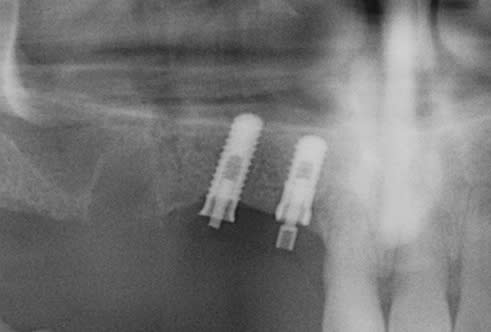

implants posés il y aurait 15 ans dentiste plus joignable

radio pas terrible

je dirais de l'IDI

sur celui de la 12 un ID one ou ID gold

sur la 13 un ID max

l'empreinte de la vis, c'est un carré? si oui, alors c'est çà.....

mais bon les radios aident pas trop non plus....;-)))))